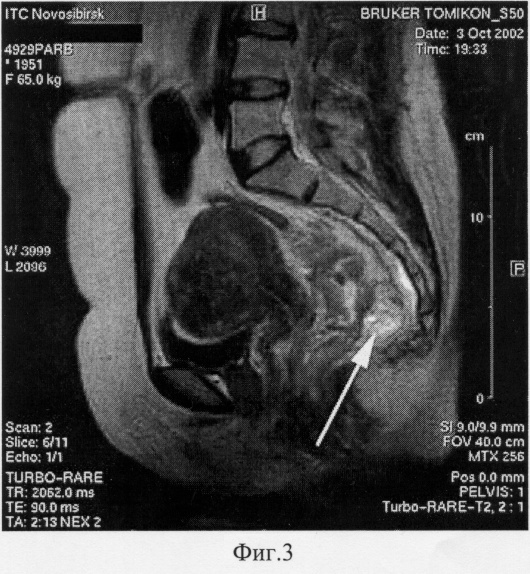

(57) Реферат: Изобретение относится к медицине и предназначено для непрямой магнитно-резонансной лимфографии. Вводят интерстициально в зону исследования вещества для магнитно-резонансного контрастирования и выполняют магнитно-резонансную томографию. Предварительно в зону исследования вводят вещество, обладающее гиалуронидазной активностью. В качестве вещества для магнитно-резонансного контрастирования используют парамагнетик, содержащий гадолиний. В качестве вещества, обладающего гиалуронидазной активностью, используют лидазу. Лидазу вводят в количестве 16-32 ед. Способ позволяет повысить эффективность непрямой магнитно-резонансной лимфографии. 3 з.п. ф-лы, 3 ил. Изобретение относится к медицине, а именно к лучевой диагностике и лимфологии, и может применяться для диагностики патологических состояний лимфатической системы, например метастазов. Известна магнитно-резонансная томография (Домбровский В.И., Арсланова Л.В., Домбровская Е.В., Черкасов М.Ф. Магнитно-резонансная томография в оценке степени распространенности рака прямой кишки. Тезисы докладов V всероссийской конференции с международным участием. Актуальные проблемы колопроктологии. Ростов-на-Дону, 2001. – С.123-124). Метод обеспечивает полипроекционность исследования и отличный тканевой контраст во взаимосвязи с окружающими тканями, однако этот метод исследования обладает достаточно низкой выявляемостью метастатического поражения лимфатических узлов из-за их низкой контрастности. Одним из наиболее информативных способов оценки состояния регионарных лимфатических сосудов и узлов является способ для рентгеноконтрастного исследования лимфатической системы (патент РФ № 2171690, МПК А 61 К 49/04, А 61 В 6/00, дата публикации 10.08.2001). Однако этот способ не дает анатомической привязки лимфатического аппарата к самому органу и патологическому субстрату. Известен способ лимфографии, при котором для улучшения всасываемости препарата, содержащего гадолиний, используют массаж участка введения, после чего выполняют магнитно-резонансную лимфографию (Ruehm S.G., Corot С. and Debatin J.F. Interstitial MR lymphography with a conventional extracellular gadolinium-based agent: assessment in rabbits. Radiology. 2001 Mar; 218(3):664-9). Способ имел экспериментальный характер и проводился на кроликах. В клинических условиях область применения такого способа ограничена – так, например, при исследовании лимфатических структур таза способ неприменим. Известен выбранный в качестве ближайшего аналога способ непрямой магнитно-резонансной лимфографии, при котором введение контрастного вещества (парамагнетика) осуществляют не непосредственно в лимфатическое русло, а подкожно (Ruehm S.G., Schroeder Т., Debatin J.F. Interstitial MR lymphography with gadoterate meglumine: initial experience in humans. Radiology 2001 Sep; 220(3).816-21). Подкожное введение gadoterate meglumine на стопе (в интерстиций) контрастировало лимфатические сосуды и узлы у людей. Недостатками способа являются низкая разрешающая способность магнитно-резонансной лимфографии, низкая точность определения (выявления) здоровых и патологически измененных сосудов и узлов лимфатической системы в их взаимосвязи с другими анатомическими образованиями и ограниченная область применения, что обусловлено низкой резорбцией парамагнетика в лимфатическое русло. Изобретение направлено на решение задачи повышения разрешающей способности магнитно-резонансной лимфографии, повышения точности определения (выявления) здоровых и патологически измененных сосудов и узлов лимфатической системы в их взаимосвязи с другими анатомическими образованиями, а также на решение задачи расширения области применения способа. Сущность изобретения заключается в том, что в способе непрямой магнитно-резонансной лимфографии, включающем интерстициальное введение в зону исследования вещества для магнитно-резонансного контрастирования и выполнение магнитно-резонансной томографии, предлагается предварительно в зону исследования вводить вещество, обладающее гиалуронидазной активностью. При этом в качестве вещества для магнитно-резонансного контрастирования может быть использован парамагнетик, содержащий гадолиний, а в качестве вещества, обладающего гиалуронидазной активностью, может быть использована лидаза. Лидаза может вводиться в количестве 16-32 ед. Применение лидазы широко известно в терапии в качестве лимфотропного средства. (Левицкий А.П., Марусич В.А. Применение препаратов гиалуронидазы для лечения резаных инфицированных ран в эксперименте. Хирургическая и ортопедическая стоматология. Вып.2. 1981. С.55-57.) Фермент гиалуронидаза, входящий в состав лидазы, катализирует процесс расщепления гиалуроновой кислоты – кислого мукополисахарида, являющегося цементирующим веществом соединительно-тканных элементов организма, расширяя поры в стенке лимфатических капилляров и разрыхляя структуру соединительной ткани, что ведет к увеличению проницаемости соединительной ткани. (Буянов В.М., Данилов К.Ю., Радзиховский А.П. Лекарственное насыщение лимфатической системы. – Киев, 1991. – 132 с., Джумабаев С.У., Файзиев И.Р., Султанов А.Т. и др. Лимфатическая терапия в хирургии. Изд-во им. Ибн-Сины, 1991. – 238 с.) Вышеописанные свойства лидазы до сих пор использовались только в терапевтических целях. Основными показаниями к применению лидазы в терапии являются контрактуры суставов, рубцы после ожогов и операций, анкилозирующий спондило артрит, гематомы и др. Раствор лидазы (1 мл) вводят в этих случаях вблизи места поражения под кожу или под рубцово-измененные ткани. Инъекции производят ежедневно или через день; курс лечения состоит из 6-10-15 и более инъекций. Лечебный эффект проявляется размягчением рубцов, появлением подвижности в суставах, устранением или уменьшением контрактур, рассасыванием гематом. Известно также использование лидазы в терапии для ускорения всасывания лекарственных веществ, вводимых под кожу и внутримышечно (местные анестетики, мышечные релаксанты, изотонические растворы и др.) Отличие заявляемого способа заключается в том, что лидазу используют в диагностике путем одноразового введения в зону проведения магнитно-резонансной лимфографии непосредственно перед введением парамагнетика, а не систематически в зону места поражения, как при терапии. При этом известное свойство лидазы – способность увеличивать проницаемость соединительной ткани, в том числе и лимфатических сосудов, – используется в новой совокупности признаков и обеспечивает достижение нового (сверхсуммарного) технического результата – повышение разрешающей способности непрямой магнитно-резонансной лимфографии, повышение точности определения (выявления) здоровых и патологически измененных сосудов и узлов лимфатической системы в их взаимосвязи с другими анатомическими образованиями, а также расширение области применения способа, что свидетельствует о неочевидности изобретения. В заявляемом изобретении предварительное введение в зону проведения непрямой магнитно-резонансной лимфографии вещества, обладающего гиалуронидазной активностью, обеспечивает повышение резорбции парамагнетика в узлы и сосуды лимфатической системы, за счет чего повышает разрешающую способность магнитно-резонансной лимфографии и точности определения (выявления) здоровых и патологически измененных сосудов и узлов лимфатической системы в их взаимосвязи с другими анатомическими образованиями, что, в конечном итоге, приводит к повышению эффективности планирования и проведения онкохирургических вмешательств. Необходимо также отметить, что предварительное введение вещества, обладающего гиалуронидазной активностью, является легкоосуществимой процедурой на любом участке проведения исследования, что способствует расширению области применения способа за счет простоты, доступности и удобства его выполнения. Использование в качестве вещества для магнитно-резонансного контрастирования парамагнетика, содержащего гадолиний, обеспечивает оптимальное накопление контрастного вещества в лимфоидной ткани. Использование лидазы в качестве вещества, обладающего гиалуронидазной активностью, позволяет повысить резорбцию парамагнетика в регионарное лимфатическое русло с помощью широко доступного средства, что упрощает осуществление способа. При этом введение лидазы в количестве 16-32 ед. обеспечивает возможность выбора оптимальной дозы парамагнетика. На фиг.1 приведены результаты непрямой тазовой магнитно-резонансной лимфографии больного З., где белая стрелка указывает на опухоль прямой кишки, а черными стрелками обозначены контрастированные лимфатические узлы мезоректума. На фиг.2 приведены результаты непрямой тазовой магнитно-резонансной лимфография больной П. (сагиттальная проекция), где визуализированы тазовые лимфатические узлы. На фиг.3 приведены результаты непрямой тазовой магнитно-резонансной лимфографии больной П., где выявлен метастаз в лимфатический узел. Способ осуществляется следующим образом. В зону исследования, куда будет введено вещество – парамагнетик, обладающее парамагнитными свойствами, предварительно вводится лидаза в дозе 16-32 Ед. Затем в эти же участки вводится вещество-парамагнетик, например “Омнискан”, из расчета в 70 micromol/kg веса. Магнитно-резонансная томография (предпочтительно – с полем 0,5-1,0 Тл, возможно – с полем 0,2-0,3 Тл) производится через 1,5-2,0 часа, например, с помощью МР-томографа Tomikon S50 фирмы Bruker (Швейцария – Германия), с полем 0,5 Тл. Лимфатические узлы контрастируемого региона представляются хорошо визуализированными на Т1-взвешенном изображении (режимы – MSSE, MSME, t-RARE). Прослеживается внутренняя структура, в том числе – синусная система лимфатических узлов, что позволяет выявить ранние патологические изменения в них. Осуществимость способа подтверждается примерами. Пример 1. Больной З. 67 лет, с опухолью нижнеампуллярного отдела прямой кишки. Для выяснения состояния регионарного лимфатического аппарата больному была проведена непрямая магнитно-резонансная лимфография по предлагаемой методике. За 2 часа до исследования в подслизистый слой прямой кишки, выше зубчатой линии введена лидаза 32 Ед, а затем 12 мл Омнискана. На фиг.1 приведены результаты исследований больного З. по предлагаемому способу: на томограмме белая стрелка указывает на опухоль прямой кишки, черными стрелками обозначены контрастированные лимфатические узлы мезоректума, видны контрастированные лимфатические узлы мезоректума, а метастатические поражения лимфатических узлов не выявляются. Больному выполнена мезоректальная эксцизия прямой кишки. В исследованном препарате мезоректума при патогистологическом исследовании метастазов в узлах не найдено, что подтверждает достоверность результатов лимфографии. Пример 2. Больная П., 51 года. У больной был диагностирован рак среднеампулярного отдела прямой кишки. Для выяснения состояния регионарного лимфатического аппарата больной была проведена непрямая магнитно-резонансная лимфография по предлагаемой методике. В подслизистый слой нижней трети прямой кишки из двух точек было введено 32 Ед лидазы и сразу же после этого 10 мл Омнискана (вес больной – 65 кг). Через 2 часа после введения парамагнетика была выполнена магнитно-резонансная томография, на которой были визуализированы тазовые лимфатические узлы (фиг.2). По задней поверхности прямой кишки визуализируется увеличенный до 1,5 см в диаметре лимфатический узел мезоректума с характерным дефектом наполнения контраста (фиг.3). Отсутствие метастатического поражения лимфатического аппарата вне собственной фасции прямой кишки определило дальнейшую хирургическую тактику. (Больной выполнена мезоректальная эксцизия прямой кишки.) Результаты лимфографии подтвердились – при патогистологическом послеоперационном исследовании в указанном лимфатическом узле выявлен метастаз опухоли, в других 14 узлах препарата мезоректума метастазов не обнаружено. Таким образом, предлагаемое изобретение позволяет повысить разрешающую способность магнитно-резонансной лимфографии и точность (выявления) определения здоровых и патологически измененных сосудов и узлов лимфатической системы в их взаимосвязи с другими анатомическими образованиями, что крайне важно для планирования адекватных онкохирургических вмешательств. Кроме того, изобретение позволяет легко и просто проводить исследования на любом участке организма, что практически не ограничивает область применения способа. Формула изобретения 1. Способ непрямой магнитно-резонансной лимфографии, включающий интерстициальное введение в зону исследования вещества для магнитно-резонансного контрастирования и выполнение магнитно-резонансной томографии, отличающийся тем, что предварительно в зону исследования вводят вещество, обладающее гиалуронидазной активностью. 2. Способ непрямой магнитно-резонансной лимфографии по п.1, отличающийся тем, что в качестве вещества для магнитно-резонансного контрастирования используют парамагнетик, содержащий гадолиний. 3. Способ непрямой магнитно-резонансной лимфографии по любому из пп.1 и 2, отличающийся тем, что в качестве вещества, обладающего гиалуронидазной активностью, используют лидазу. 4. Способ непрямой магнитно-резонансной лимфографии по п.3, отличающийся тем, что лидазу вводят в количестве 16-32 ед. РИСУНКИ